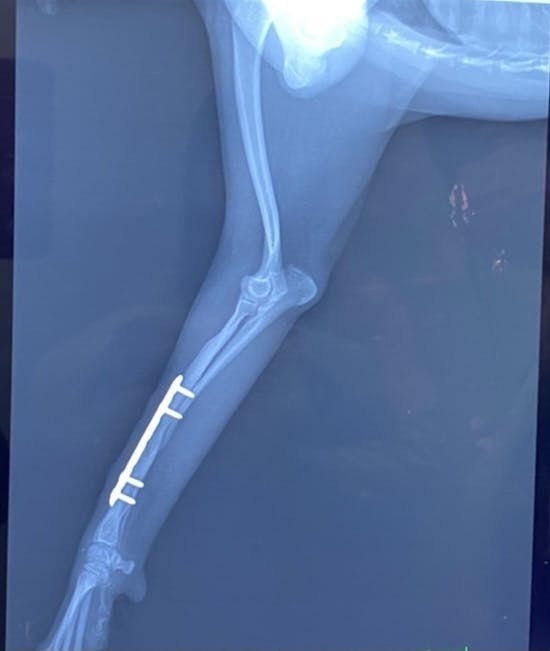

骨が少しずつくっついていて年明けには写真のように入っているボルド2本が取れる予定です。先生からも歩き方や体重のかけ方、筋肉量は問題ないとのことだったので一安心しています。